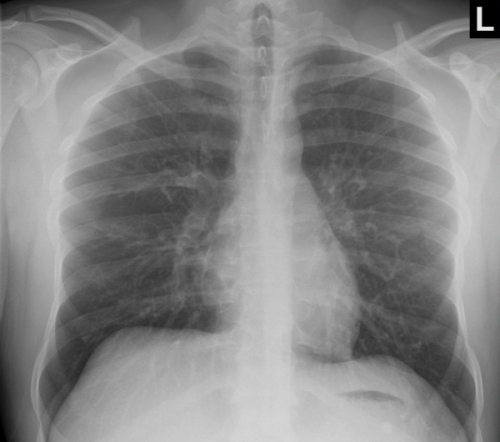

Tool to train medical student's eyes as to what a normal chest x-ray looks like, with over 500 consecutive normal images.